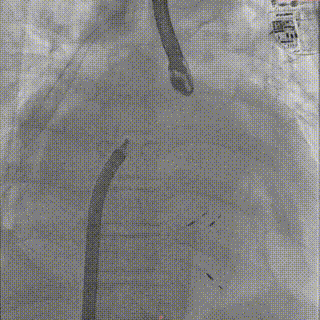

患者在全麻状态下,经超声引导建立右侧股静脉入路,送入房间隔穿刺系统。于上下腔连线中部偏下、主动脉短轴切面中部略偏后位置尝试穿刺,多次推送穿刺针均见帐篷样隆起,但穿刺点高度均偏高,调整穿刺针位置后仍未能获得合适的房间隔穿刺高度。遂决定先于较高位置行房间隔穿刺,首次穿刺高度为6.14cm,将房间隔导丝送至左上肺静脉作为定位参照。更换房间隔穿刺系统后再次尝试穿刺,仍难以达到理想高度。

怎么上穿刺鞘攻克巨大左房伴转位穿刺难关!温医大附一院周浩教授团队创新应用“导丝定位+可调弯鞘”技术完成高难度TEER手术_https://www.jmylbn.com_新闻资讯_第12张

首次房间隔穿刺

怎么上穿刺鞘攻克巨大左房伴转位穿刺难关!温医大附一院周浩教授团队创新应用“导丝定位+可调弯鞘”技术完成高难度TEER手术_https://www.jmylbn.com_新闻资讯_第13张

首次房穿高度

怎么上穿刺鞘攻克巨大左房伴转位穿刺难关!温医大附一院周浩教授团队创新应用“导丝定位+可调弯鞘”技术完成高难度TEER手术_https://www.jmylbn.com_新闻资讯_第14张

房间隔导丝送至左上肺静脉作为定位参照

怎么上穿刺鞘攻克巨大左房伴转位穿刺难关!温医大附一院周浩教授团队创新应用“导丝定位+可调弯鞘”技术完成高难度TEER手术_https://www.jmylbn.com_新闻资讯_第15张

TEE 3D视角下房穿定位导丝

随后更换为可调弯房间隔穿刺鞘,在较定位导丝更靠前、靠下的位置进行穿刺,最终穿刺高度降至4.94cm。因患者房间隔组织异常坚韧,穿刺鞘多次尝试均未能通过,遂使用6mm外周球囊对穿刺部位进行扩张,撤处出原留置在左房内的定位导丝,随后顺利置入SGC。